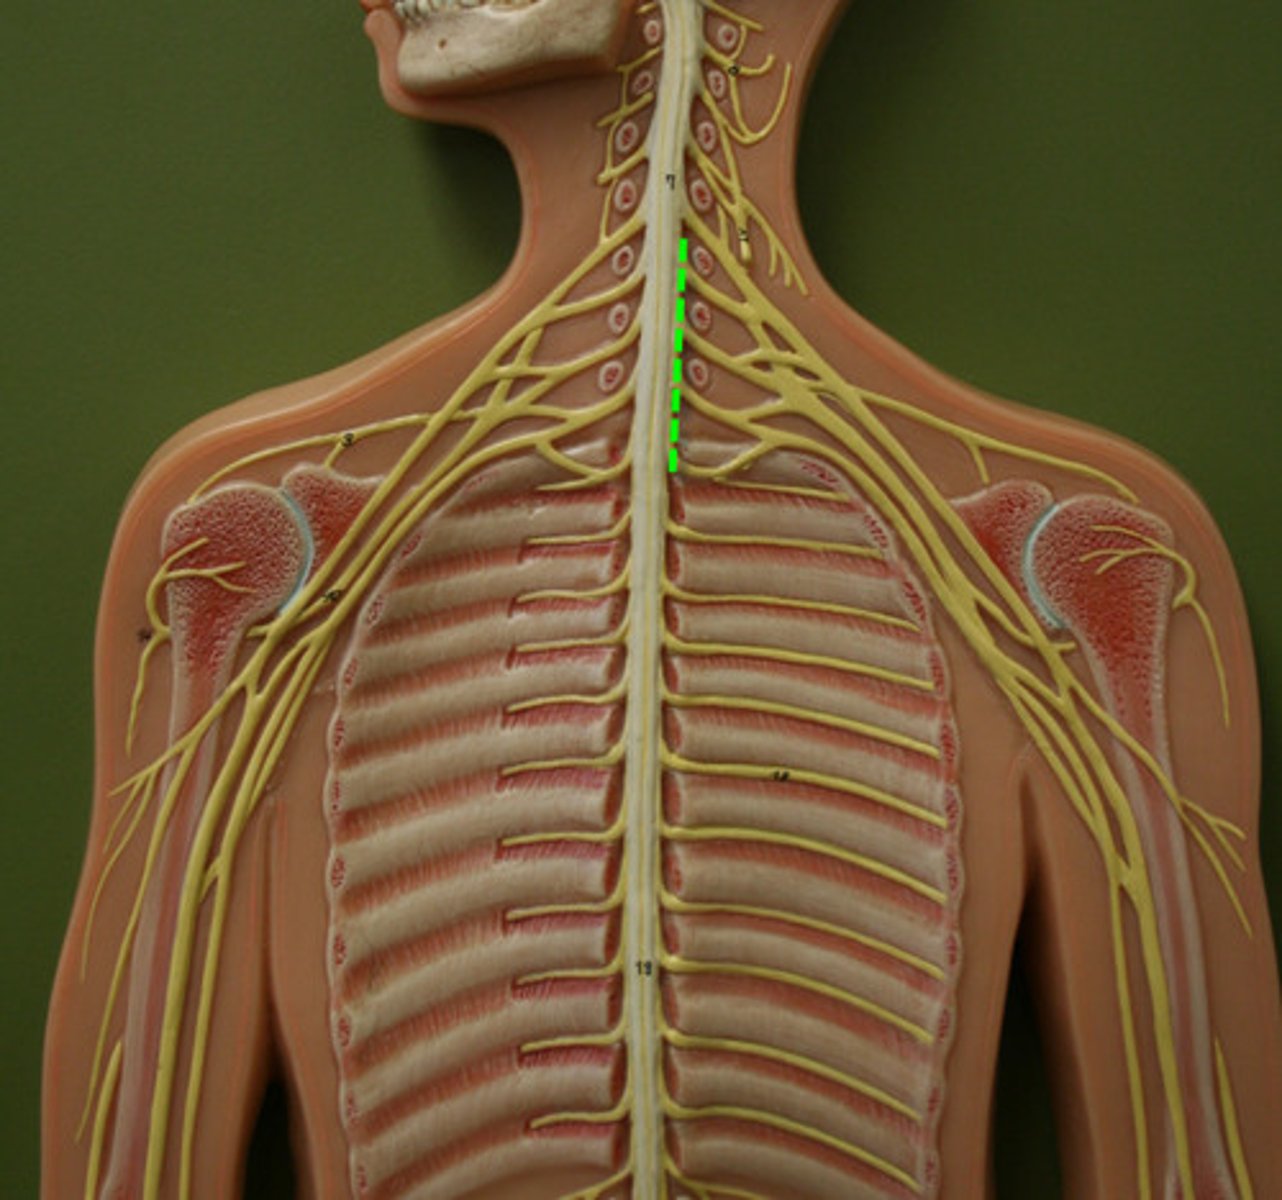

cervical enlargement

lumbar enlargement

conus medullaris

cauda equina